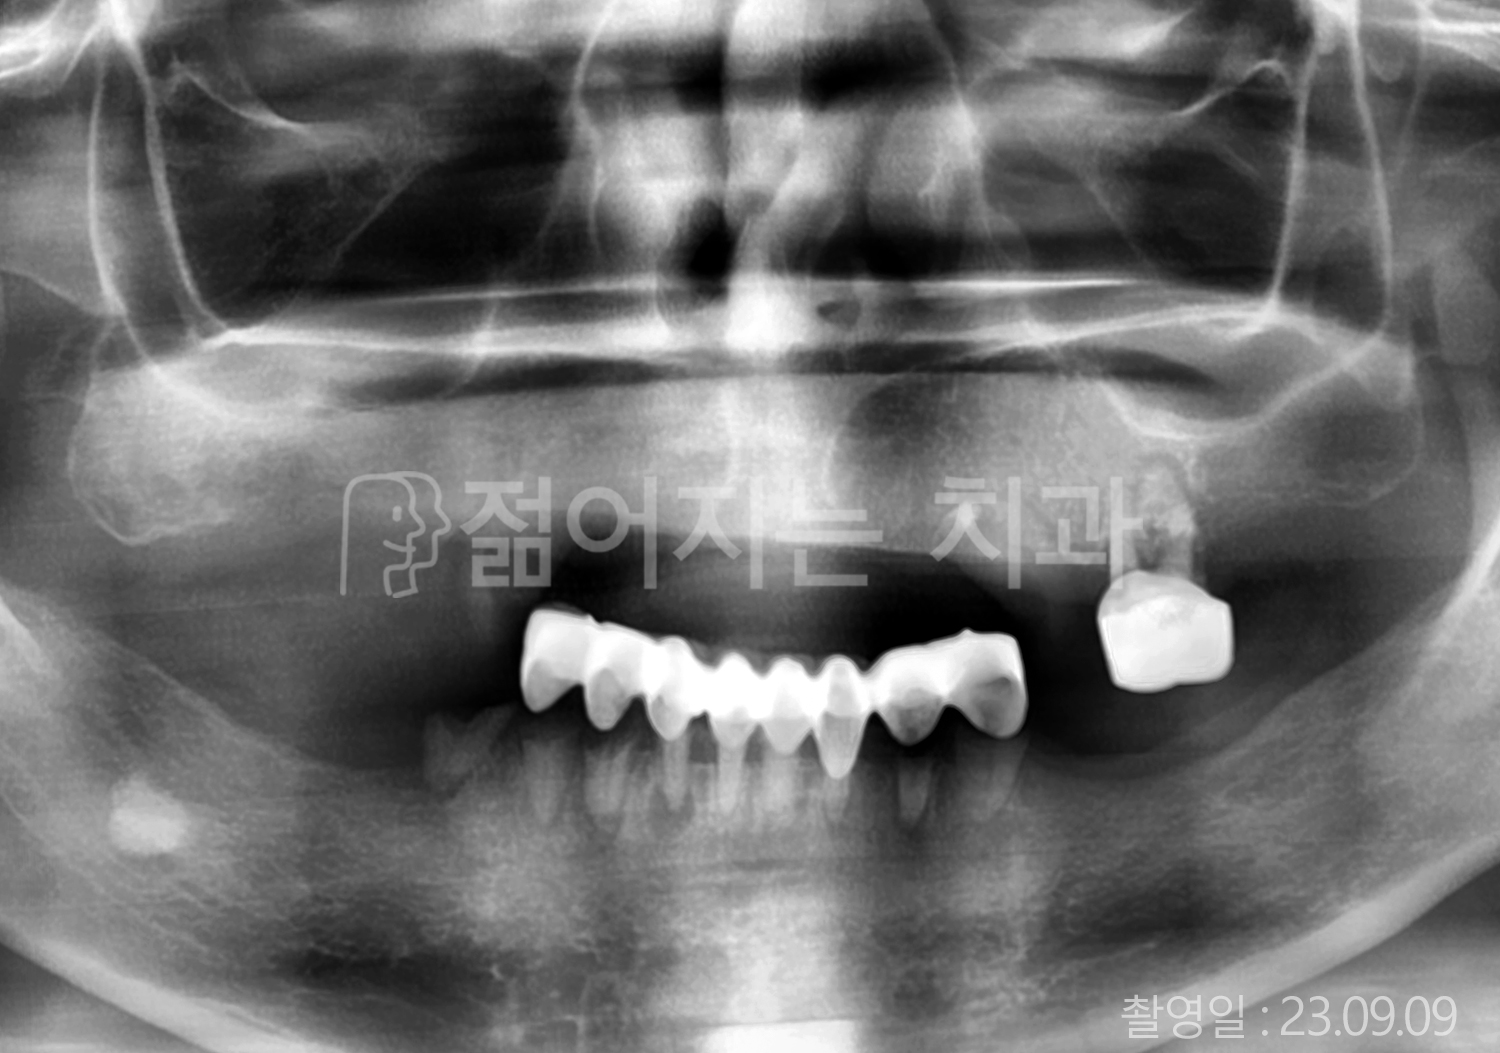

• 60대 전체치아 10개 이상 임플란트

• 50대 전체치아 10개 이상 임플란트

• 70대 고혈압, 암, 갑상선 질환 전체치아 10개 이상 임플란트

• 60대 고혈압, 당뇨, 고지혈증 전체치아 10개 이상 임플란트

• 40대 당뇨 전체치아 10개 이상 임플란트

• 70대 전체치아 10개 이상 임플란트

• 60대 당뇨 전체치아 10개 이상 임플란트

• 70대 고혈압, 당뇨 전체치아 10개 이상 임플란트